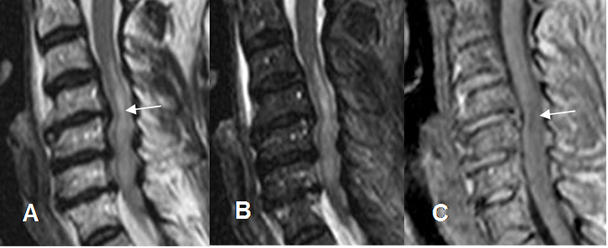

Fig 176 A. Lesión ligamentaria.

A: RM sagital en T2 y B: RM sagital en STIR. Luxación de facetas articulares, con anterolistesis de C5, sobre C6. Ligamento común anterior rodeado por líquido, pero permanece íntegro. (Flechas delgadas). Interrupción de los ligamentos común posterior y amarillo, por ruptura. (Flechas gruesas). Edema en los tejidos blandos posteriores, por lesión de los ligamentos interespinosos.

(Puntas de flecha.). Se aprecia escaso líquido anterior al cuerpo de C6.

Fig 176 B. Lesión ligamentaria.

A: TAC reconstrucción lateral y B: RM sagital en T2. Anterolistesis traumática, con aumento del espacio retrofaringeo y colección anterior. Adelgazamiento del ligamento común anterior (Flechas delgada) y ruptura del posterior. (Flecha gruesa). Adicionalmente hay compresión y alteración en la señal medular, por edema. (Puntas de flecha).